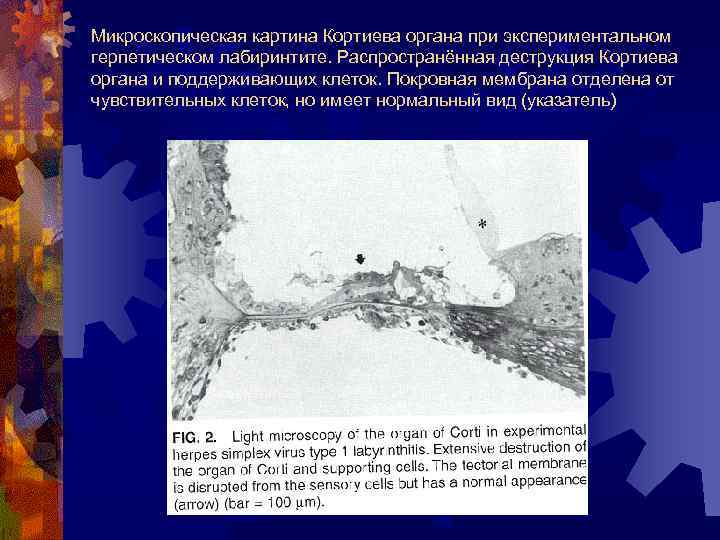

Микроскопическая картина Кортиева органа при экспериментальном герпетическом лабиринтите. Распространённая деструкция Кортиева органа и поддерживающих клеток. Покровная мембрана отделена от чувствительных клеток, но имеет нормальный вид (указатель)